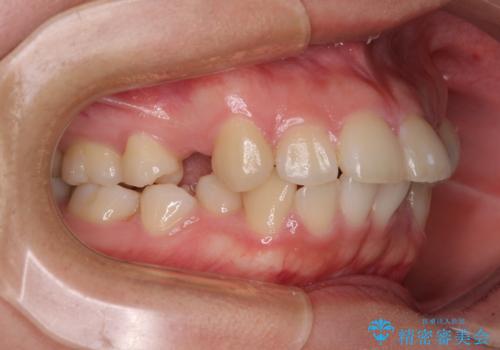

地元で矯正治療を始める予定で上顎左右第1小臼歯2本を抜歯したものの、その後転居したため治療が滞っているとのことでした。

上下ともに歯列が前方に突出していたため、上下左右の第一小臼歯4本を抜去する方針(既に上顎は抜歯されています)で、ワイヤー装置による矯正治療を行うこととしました。